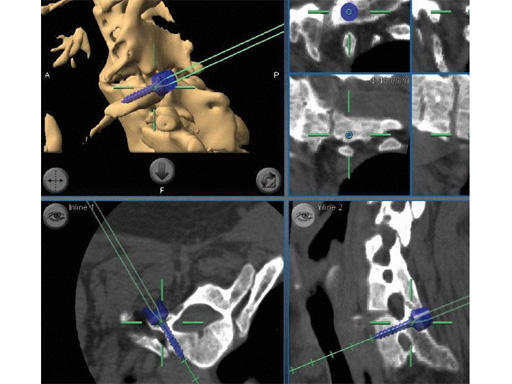

Two recent clinical studies demonstrated improved screw accuracy with isocentric image-intensification-based CT navigation compared to conventional image intensification in > 300 patients undergoing minimally invasive lumbar fusion [9, 10]. Stereotactic navigation is especially useful in patients with more complex anatomy, such as significant spondylolisthesis or degenerative scoliosis. For example, the combination of microsurgery, tubular access approach, CAS and modern instrumentation technology allow decompression and reduction of lumbar spondylolisthesis and stenosis with minimal blood loss and injury to the surrounding musculature (Fig 5). Navigation can also be used to determine the best trajectory for intervertebral cage placement and for transsacral fixation [11]. In the lumbar spine it can be used to determine the length of rods and to align screws during a multilevel fusion so that the percutaneous rod placement is facilitated (Fig 6). Stereotactic navigation has also enabled the minimally invasive resection of odontoid masses via a transnasal route, which is a significant improvement when compared to conventional maximally invasive transoral surgery [12, 13] (Fig 7).

Fig 6ab a Intraoperative screenshot of multilevel lumbar instrumentation. By simulating multiple screws a screw angle and trajectory can be chosen that will facilitate smooth insertion of rods. Distance between screws and rod length can also be determined.

b Postoperative lateral x-ray in same patient. This case combined a lateral translumbar approach for interbody fusion L2L4, a transsacral discectomy, instrumentation, and fusion for L4S1 and percutaneous pedicle screw instrumentation from L2S1 using 3-D-nav.